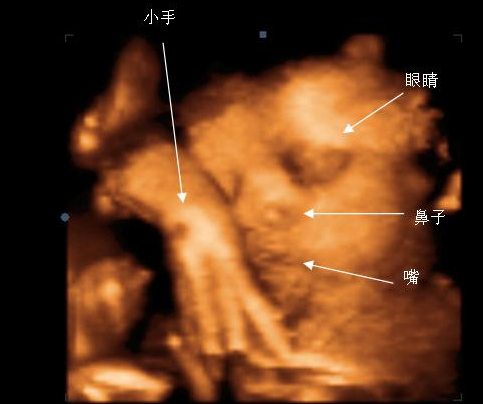

胎儿的健康是孕妈的最为重要的,因此,孕期排畸检查也是尤为重视的。泉州福兴医院排畸项目是采用三维彩超。三维彩超表面成像用于产科检查,不仅可观察到胎儿成长的过程,而且可以检查胎盘、羊水及脐带的变化,更重要的是可作为诊断胎儿畸形的主要手段。

泉州福兴妇产医院引进先进的美国GE-E8四维彩超仪,三维彩超和四维彩超的区别主要在于在一个“时间维”,也就是说,三维彩超是图片,是静态的

美国GE-E8四维数字彩超超越了传统超声的限制,全面升级的技能能够显示您未出生宝宝的实时动态活动图像,一样的排畸,不一样的临床效果。较三维彩超更清晰真实,其出色的人体工程学设计能直观、立体的观察和显示人体器官的动态和三维结构。